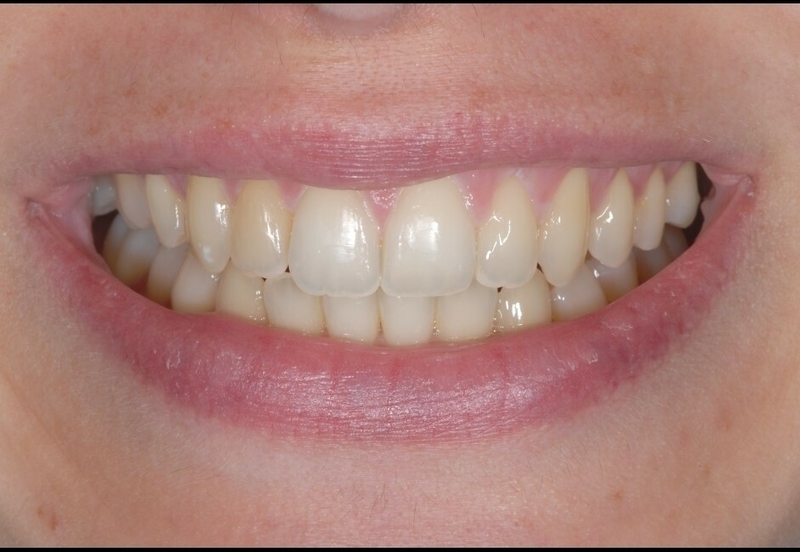

Cas 1 - Blanchiment dentaire

Avant

Après